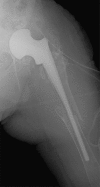

Two-stage revisions with antibiotic-loaded spacers have gained popularity for treating infected hip-joint arthroplasties. The aim of this prospective study was to assess patient functionality between stages and treatment impact on duration of hospital stay and to describe related complications. Sixty-one consecutive patients with infected hip arthroplasties underwent two-stage revision with preformed spacer implantation. Mean Harris Hip and Merle d'Aubigné scores between the two stages were 39.9 and 7.6, respectively. Forty-six patients (75.4%) were able to leave hospital between stages. Spacer dislocation occurred in 16.4%. No cases of spacer breakage were noted. Preformed cement spacers provide acceptable functional outcome between revision hip arthroplasty stages and facilitate the surgical procedure without increasing mechanical complication rates.